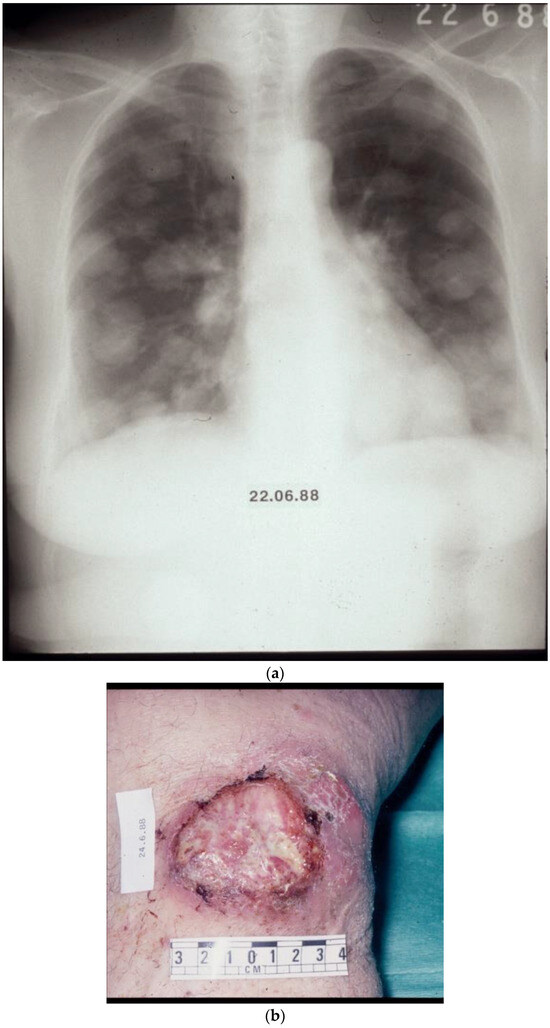

Figure 3.

(a,b) What the ancients would have called a “therioma”. Before and after chemotherapy.

Figure 3a,b—The case of a patient with numerous visceral and cutaneous lesions, some ulcerating with odorous discharge, intolerable to the patient and the carers. This patient was referred from a palliative care unit to the Westminster Hospital in London, UK. Figure 3a illustrates a selected lesion before the commencement of chemotherapy with the DJV3 combination, (dacarbazine, vincristine, vindesine, vinblastine, carboplatin) and Figure 3b, after treatment, with significant palliation of the target lesion shown and the complete resolution of other masses. (Image reproduced in colour from Retsas, S. et al. [23].)

Figure 4a,b—This patient had disseminated melanoma with multiple pulmonary lesions and an ulcerating mass on the right knee, the site of the primary lesion. Treated in the late 1980s with combination chemotherapy with the DJV3 combination (see above, Figure 3a,b). Resolution with treatment of pulmonary lesions and healing of the soft tissue mass overlying the right knee. (Image reproduced and supplemented in colour from Retsas, S. et al. [23].)